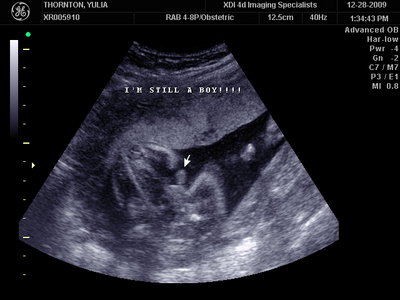

Ну ладно, тогда и я нашего писюна покажу  Надеюсь, Джеффри на меня не обидится Вот это в 23 недели: (там оборудование переключалось из режима 3Д в обычный 2Д)

| Вложения: |

MY BABY SONO!_2_15.JPG [ 112.35 КБ | Просмотров: 1048 ]

Sweetheart75 писал(а): Ну ладно, тогда и я нашего писюна покажу  Надеюсь, Джеффри на меня не обидится Вот это в 23 недели: (там оборудование переключалось из режима 3Д в обычный 2Д) Oоо, такое достоинство невозможно не заметить  А в 30 недель так вообще!